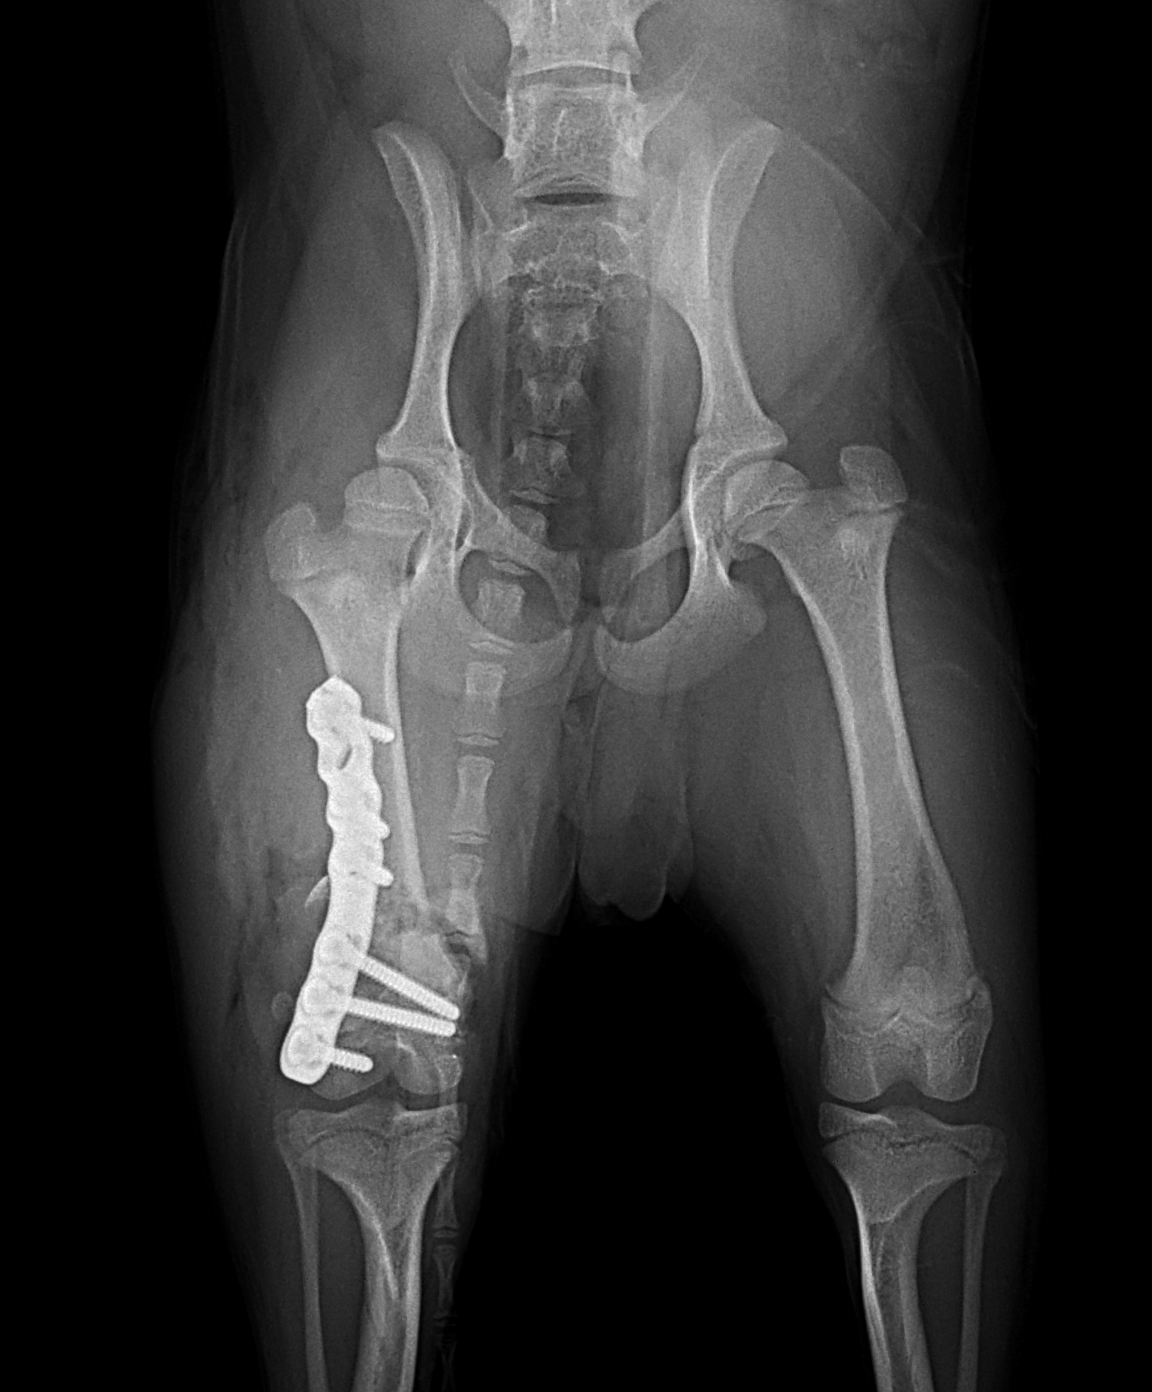

幼犬の大腿骨遠位の骨折です。幼犬は治癒能力が高く、仮骨の形成が早期に起こります。しかしながらこの時期は骨質が大変柔らかく固定には注意が必要です。本来であれば成長板をまたぐ固定は避けたいところですが、やむを得ず軽量のTitanium Locking Plateを用いて固定術を行いました。早期に抜釘することになります。